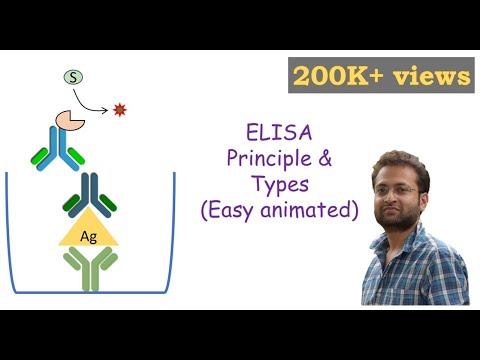

ELISA | Enzyme linked immonosorbent assay | ELISA test | Types of ELISA | Direct and Indirect ELISA

Types

Direct

Indirect

Sandwich

Competitive